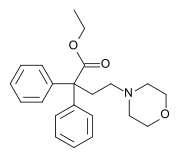

Open chain opioids

Amidones

- Dextromethadone

- Dipipanone

- Isomethadone=

- Levoisomethadone

- Levomethadone

- Methadone

- Methadone intermediate

- Normethadone

- Norpipanone

- Phenadoxone (heptazone)

Structures